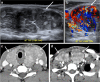

Focal and diffuse thyroid abnormalities are commonly encountered during the interpretation of computed tomography (CT) exams performed for various clinical purposes. These findings can often lead to a diagnostic dilemma, as the CT reflects the nonspecific appearances. Ultrasound (US) examination has a superior spatial resolution and is considered the modality of choice for thyroid evaluation. Nevertheless, CT detects incidental thyroid nodules (ITNs) and plays an important role in the evaluation of thyroid cancer. In this pictorial review, we cover a wide spectrum of common and uncommon, incidental and non-incidental thyroid findings from CT scans. We also discuss the most common incidental thyroid findings, best practices for their evaluation, and recommendations for their management. In addition, we explore the role of imaging in the assessment of thyroid carcinoma (before and after treatment) and preoperative thyroid goiter, as well as localization of ectopic and congenital thyroid tissue.

Teaching points: • Thyroid disorders tend to have non-specific CT appearances. • ITNs are common on neck CT. • ITN management depends on nodule size, age, health status, lymphadenopathy, and invasion. • CT is used in assessment of cancer extension, mass effect, invasion, and recurrence. • CT plays a role in preoperative planning in patients with symptomatic goiter.